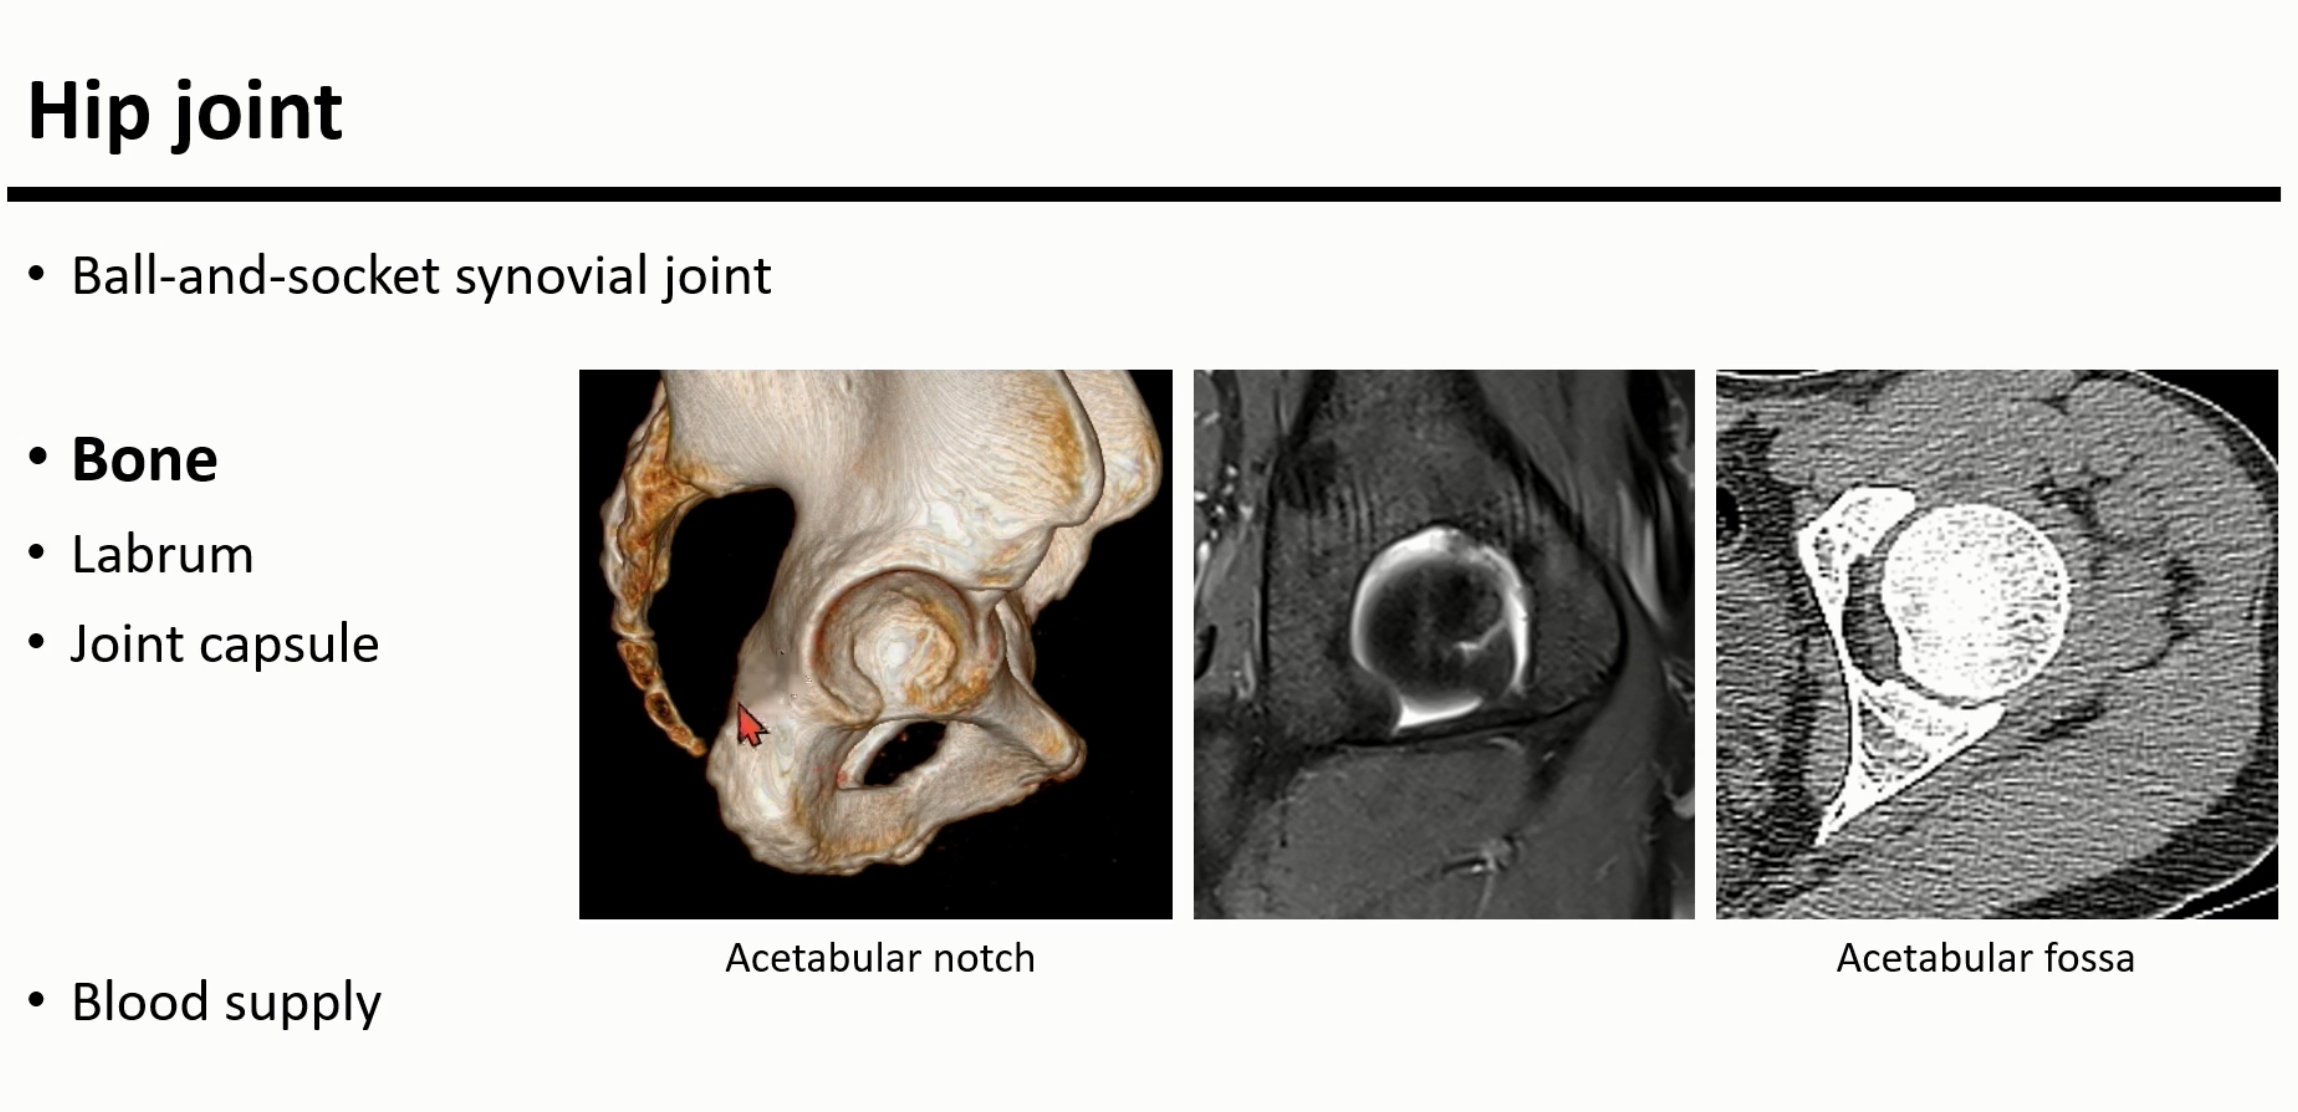

hip joint는 ball and socket joint로, 다양한 움직임을 가능하게 하는 관절이다

가장 좌측의 사진에서 acetabular notch는 아래 방향에 위치하고, MRI상에서 보이는 transverse ligament로 구성됨.

acatabulum의 관절 중 cartileage가 아닌 fat으로 구성된 acetabular fossa가 존재함.

Femur head는 cartileage로 거의 덮여있지만, 중심부는 cartileage가 없는 곳이 존재하는 구역이 있음.

이 구역을 Fovea capitis라고 함.

Ligamentum teres는 transverse ligament부터 시작해서, Fovea capitis를 연결하는 구조이며, obturator artery의 분지를 포함함. MRI상 hypo-intense한 cord-like structure이나, fovea capitis에 부착되는 부위에서는 정상에서도 다소 high signal을 보일 수 있다.